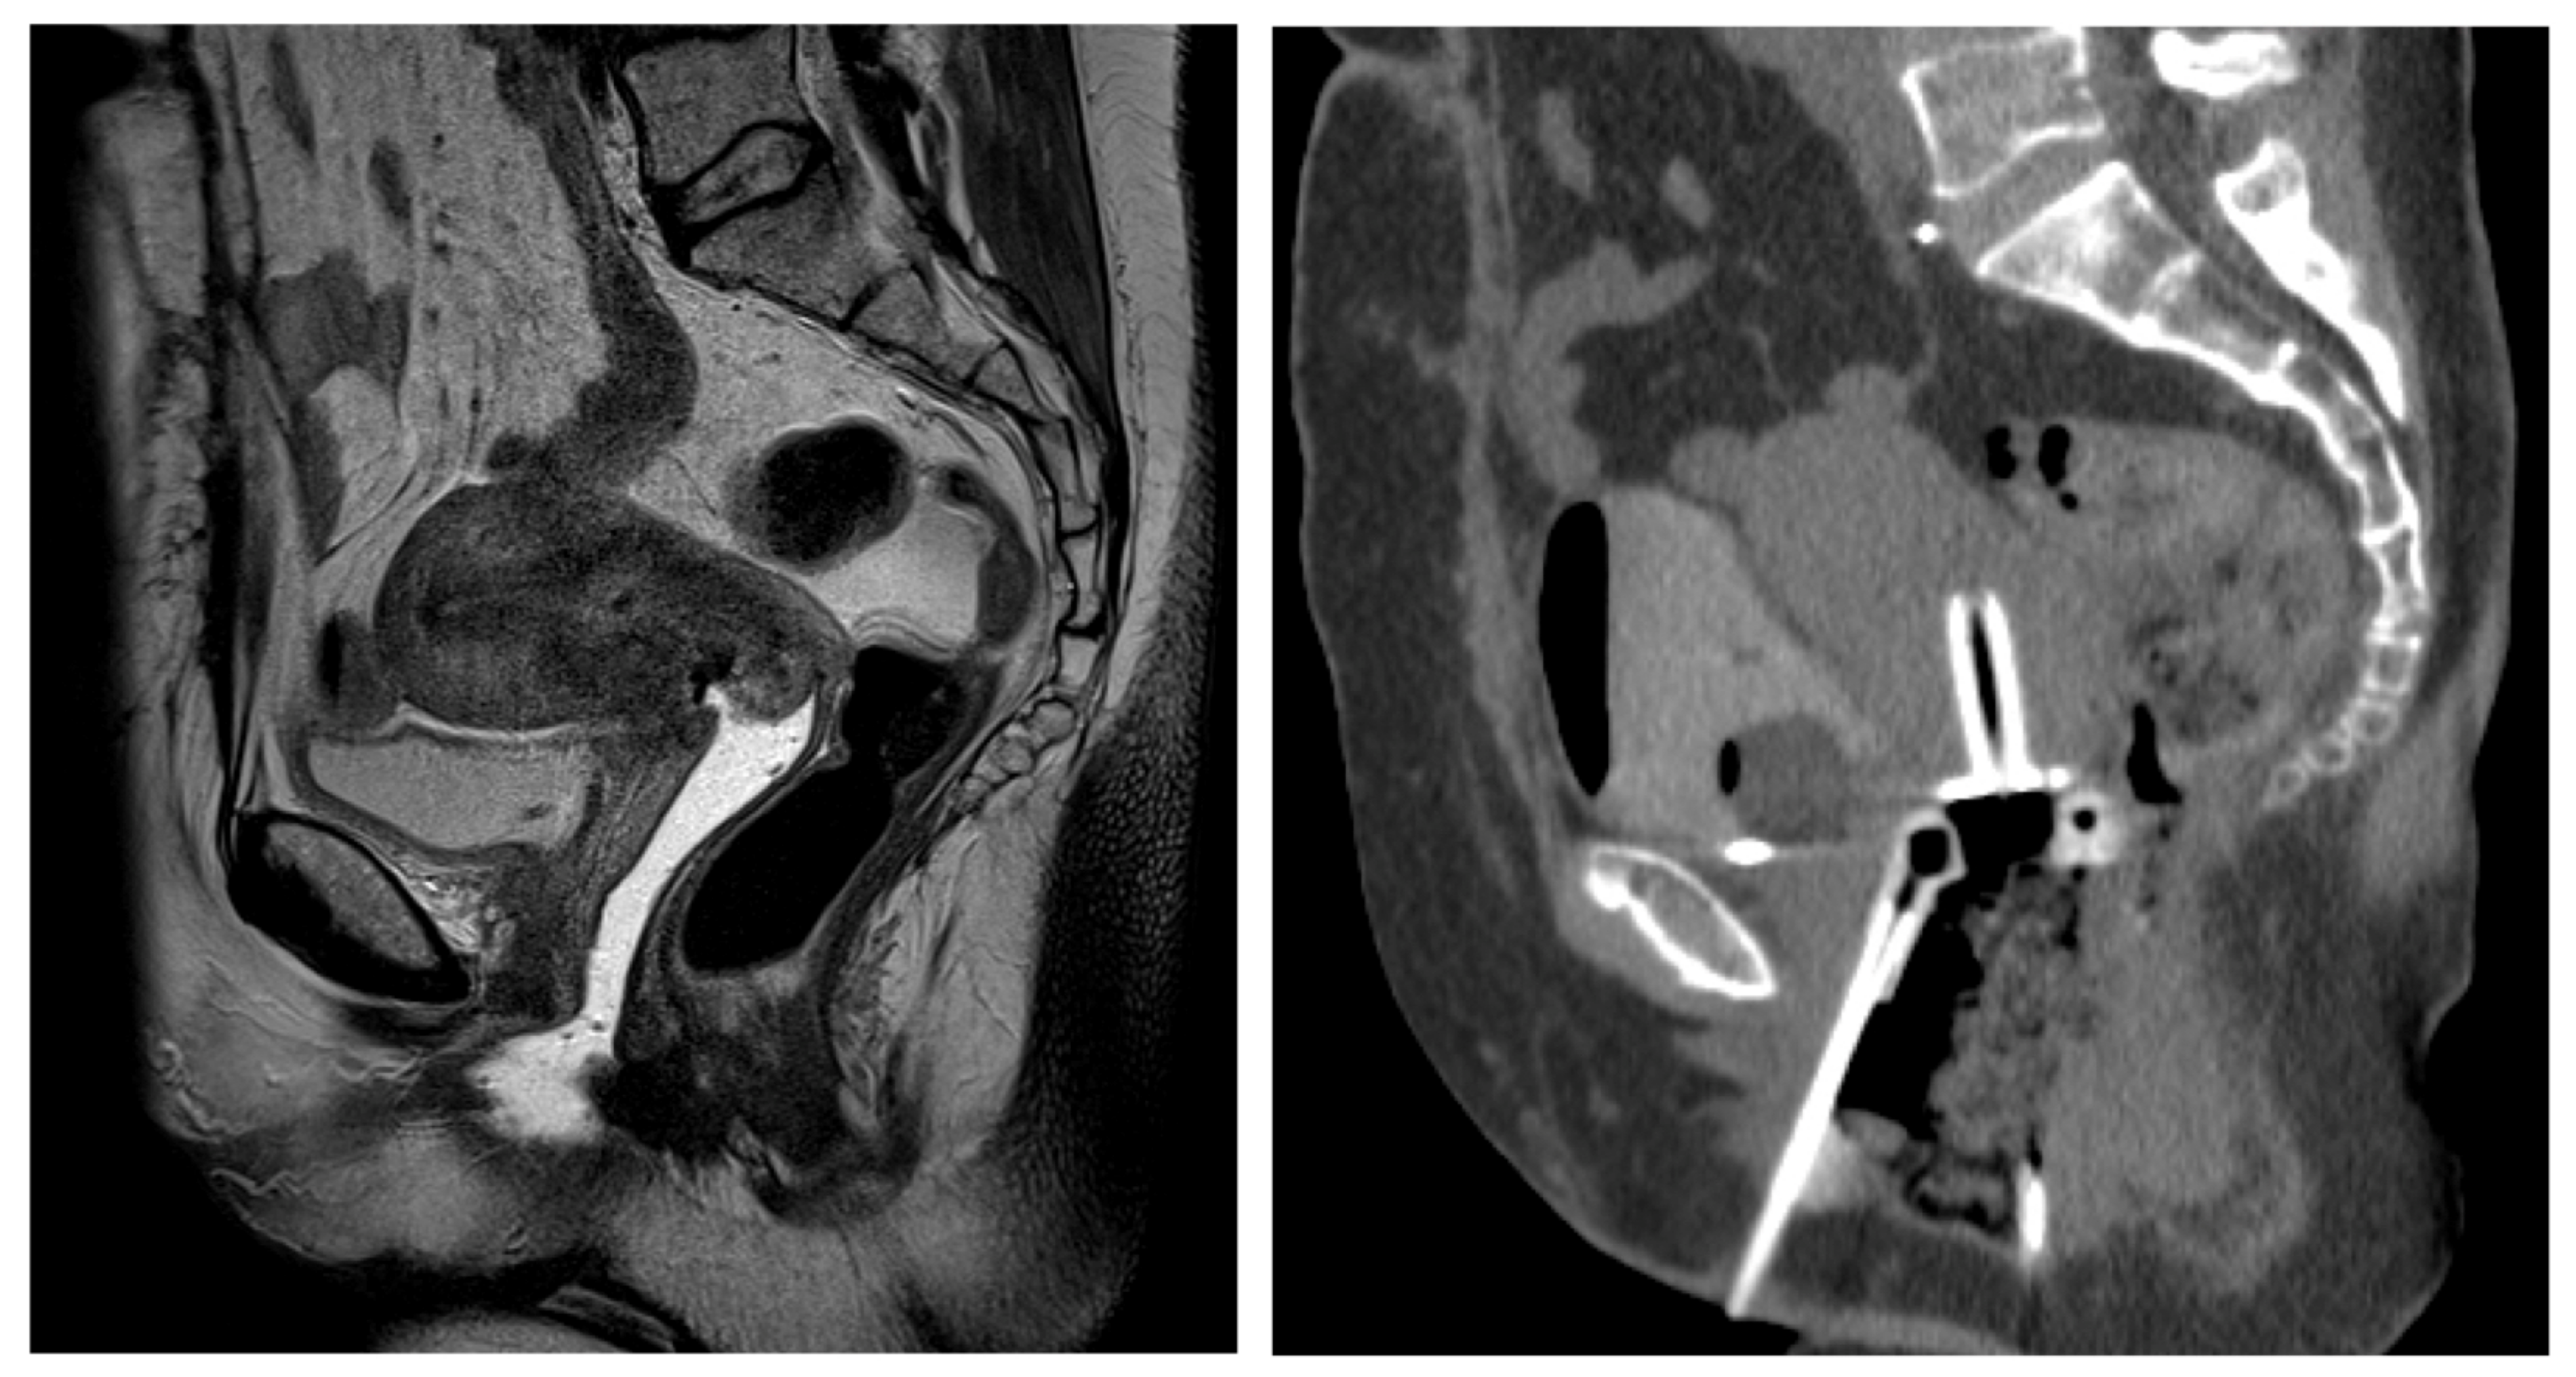

The Fusion of MRI and CT in the Planning of Brachytherapy for Cancer of the Uterine Cervix

2. Materials and Methods